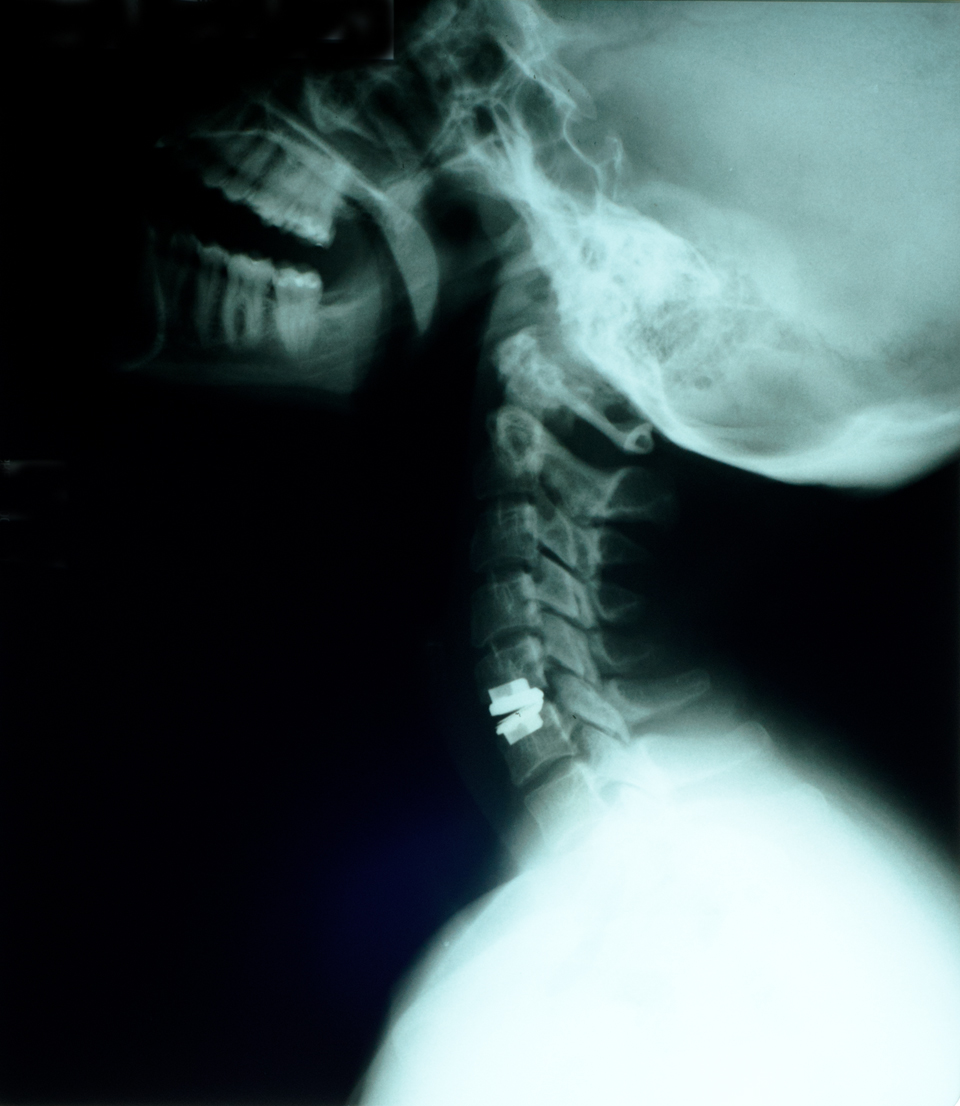

LONDON, Sept. 8, 2016 /PRNewswire/ — The cervical Total Disc Replacement (CTDR) device is used to treat patients suffering from Degenerative Disc Disorders (DDD). Neck pain is the major cause for the development of DDD in the cervical region of the spine. Cervical disc replacement surgery is performed for treatment of DDD, where the degenerated disc is removed surgically and an artificial disc is implanted in the vertebra. This is a Minimal Incision Surgery (MIS) and results in quick recovery post-surgery, short hospital stay, and low revision surgery rate.

Conventionally, DDD is treated through spinal fusion surgery, but due to the high rate of revision surgery and increasing the prevalence of adjacent segment disc degeneration post fusion surgery, doctors prefer cervical disc replacement over spinal fusion. Major players in the market are proactively providing training to spine surgeons, thus, ensuring efficient handling of their respective products.